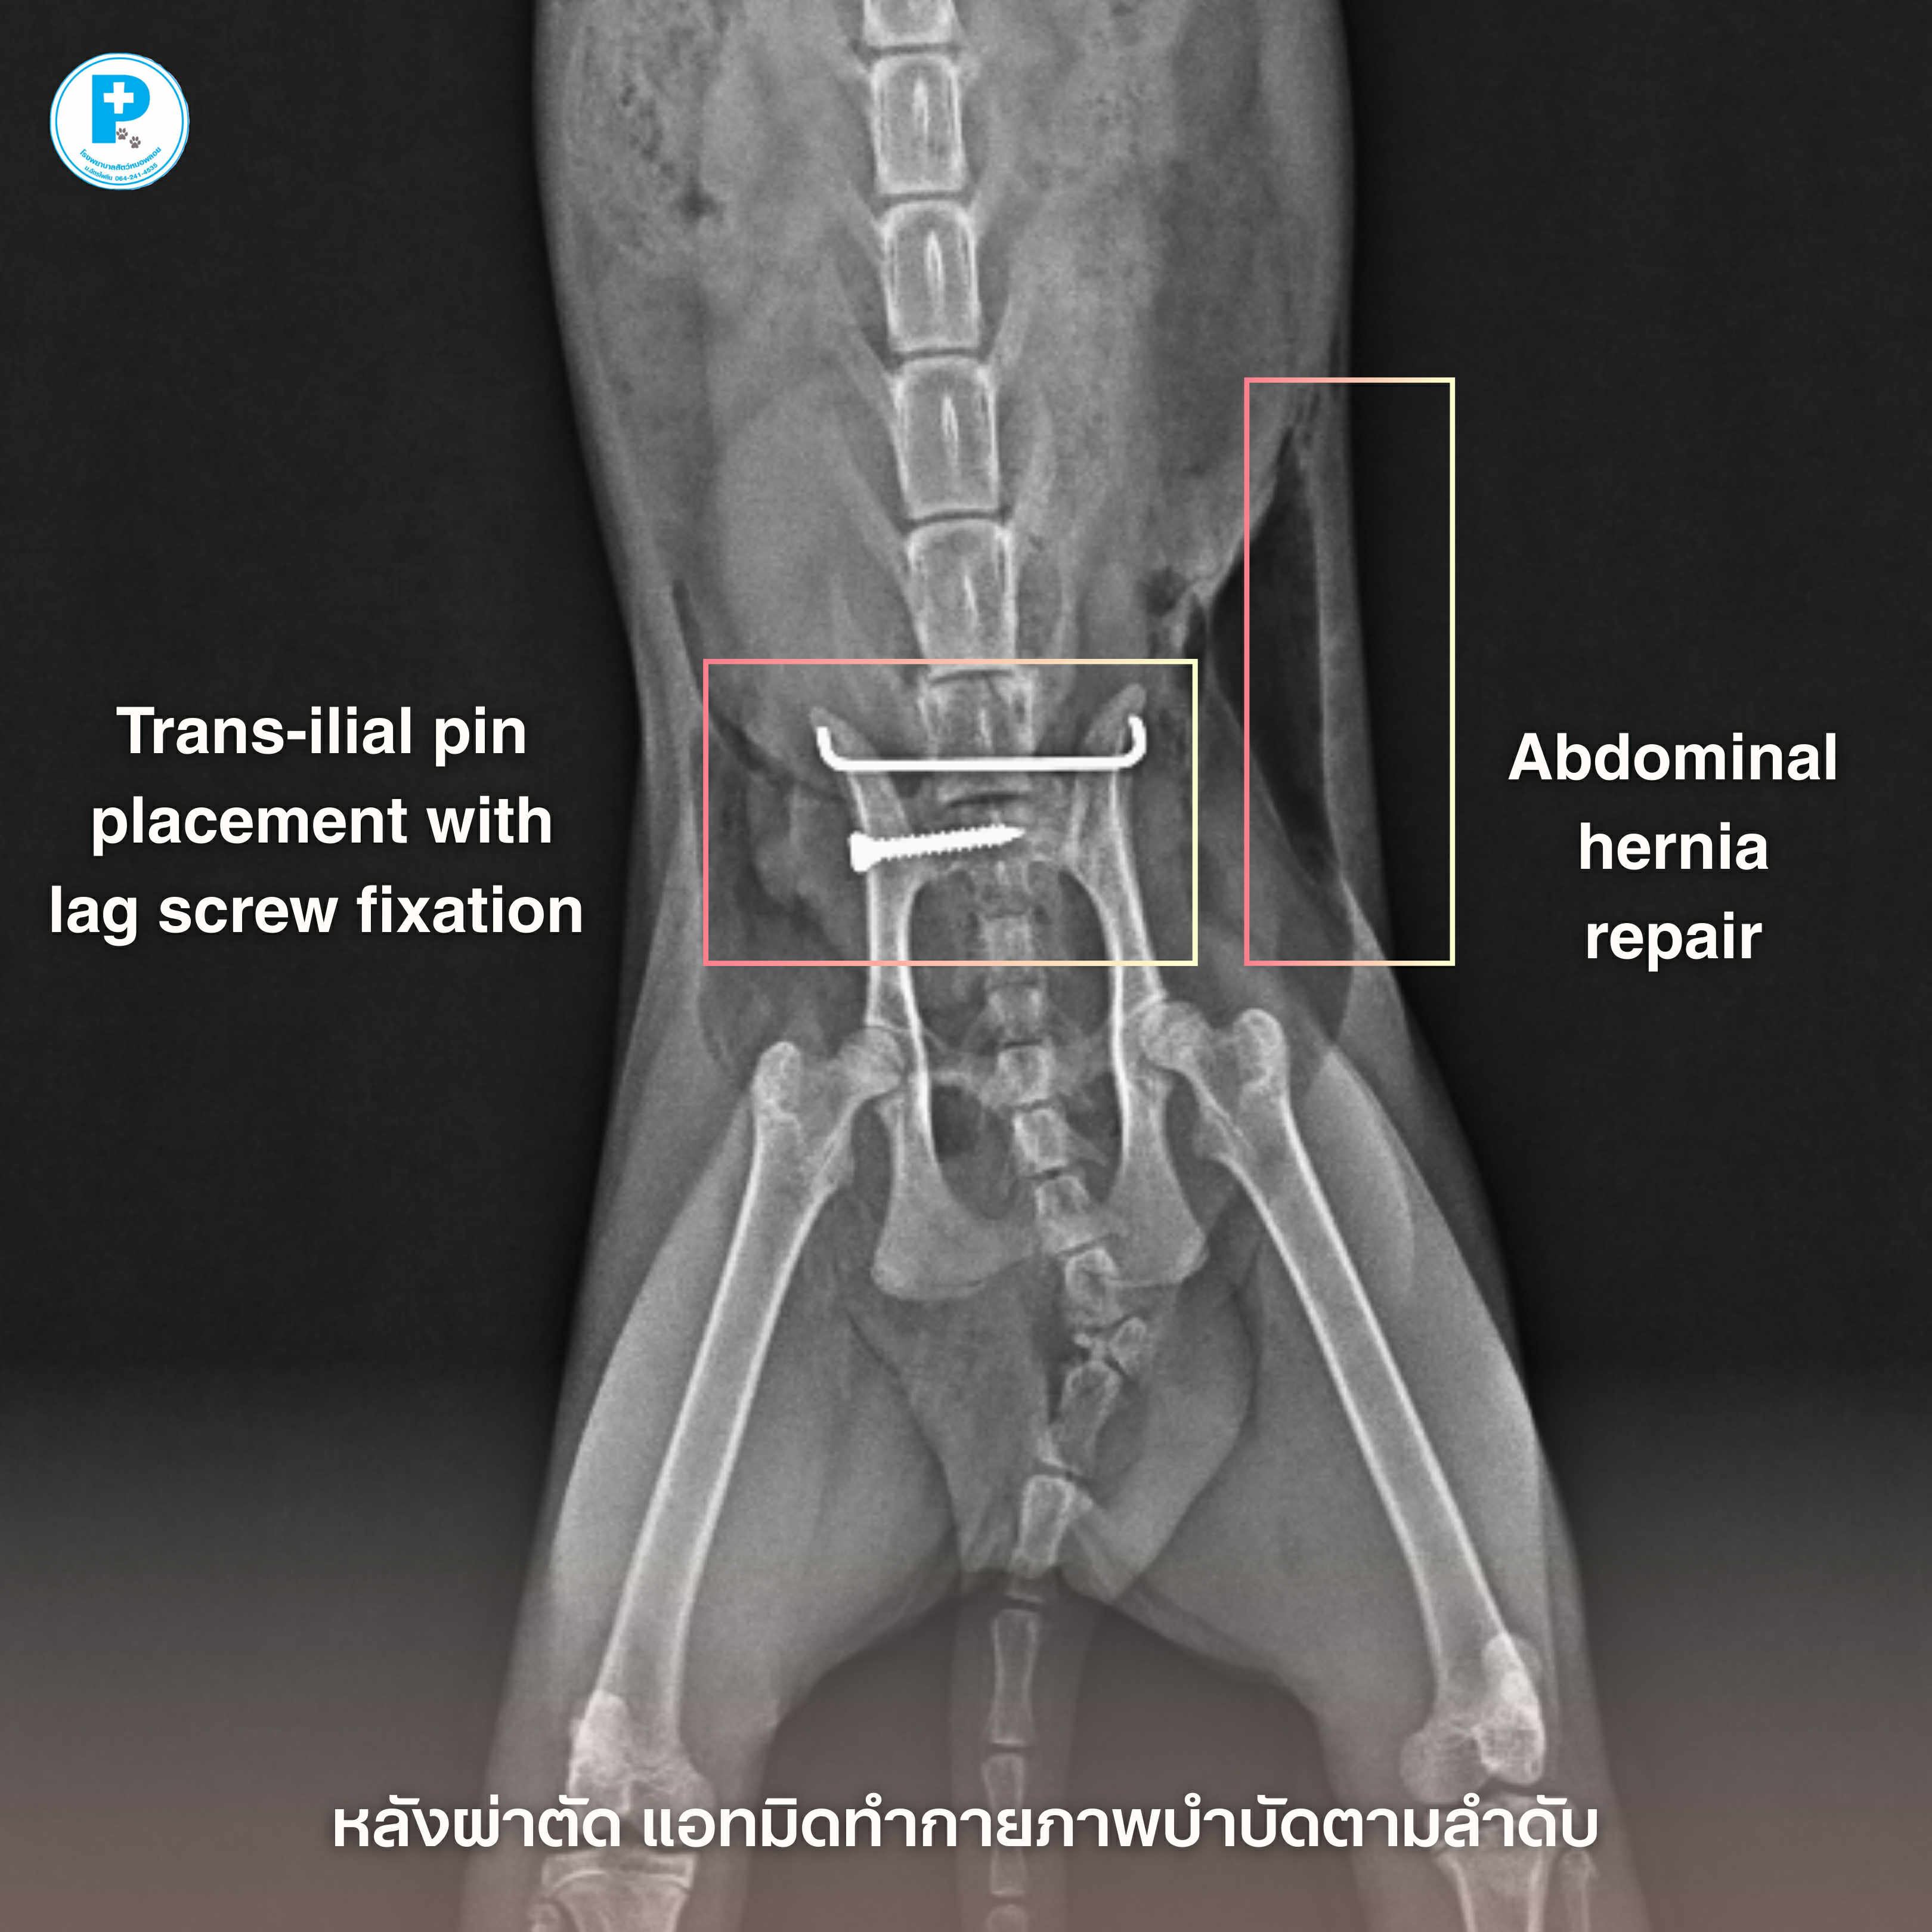

- น้องดำประสบอุบัติเหตุอย่างรุนแรง กระดูกเชิงกรานเคลื่อนทั้งสองข้าง (Both sacroiliac luxation) ร่วมกับภาวะไส้เลื่อนช่องท้อง (Abdominal herniation)

ก่อนผ่าตัด น้องดำมาที่รพส.ด้วยอาการ

• ขาหลังอ่อนแรง

• เจ็บเมื่อจับบริเวณเชิงกราน

• ผนังช่องท้องฉีกขาด ทำให้อวัยวะภายในเคลื่อนออกจากตำแหน่งปกติ

แนวทางการรักษา

ผ่าตัดจัดกระดูกด้วย Trans-iliac pin placement ร่วมกับ lag screw fixation

ซ่อมแซมผนังช่องท้อง (Abdominal hernia repair)การบาดเจ็บลักษณะนี้ หากปล่อยไว้อาจส่งผลต่อระบบประสาท การขับถ่าย และคุณภาพชีวิตระยะยาว

หลังผ่าตัด วางแผนทำกายภาพบำบัดเป็นลำดับ ควบคุมความเจ็บปวดอย่างใกล้ชิด ติดตามภาพรังสีประเมินการยึดติดของกระดูก

อุบัติเหตุอาจเกิดขึ้นได้เสมอ แต่การวินิจฉัยที่แม่นยำและการผ่าตัดที่เหมาะสม ช่วยให้เขากลับมายืนได้อีกครั้ง

ผ่าตัด: สพ.ญ.ณัฐฐ์ธวรรณ โสภิพันธ์ (หมอพลอย)

เรียบเรียง: น.สพ.นรภัทร โสภิพันธ์ (หมอพีท)